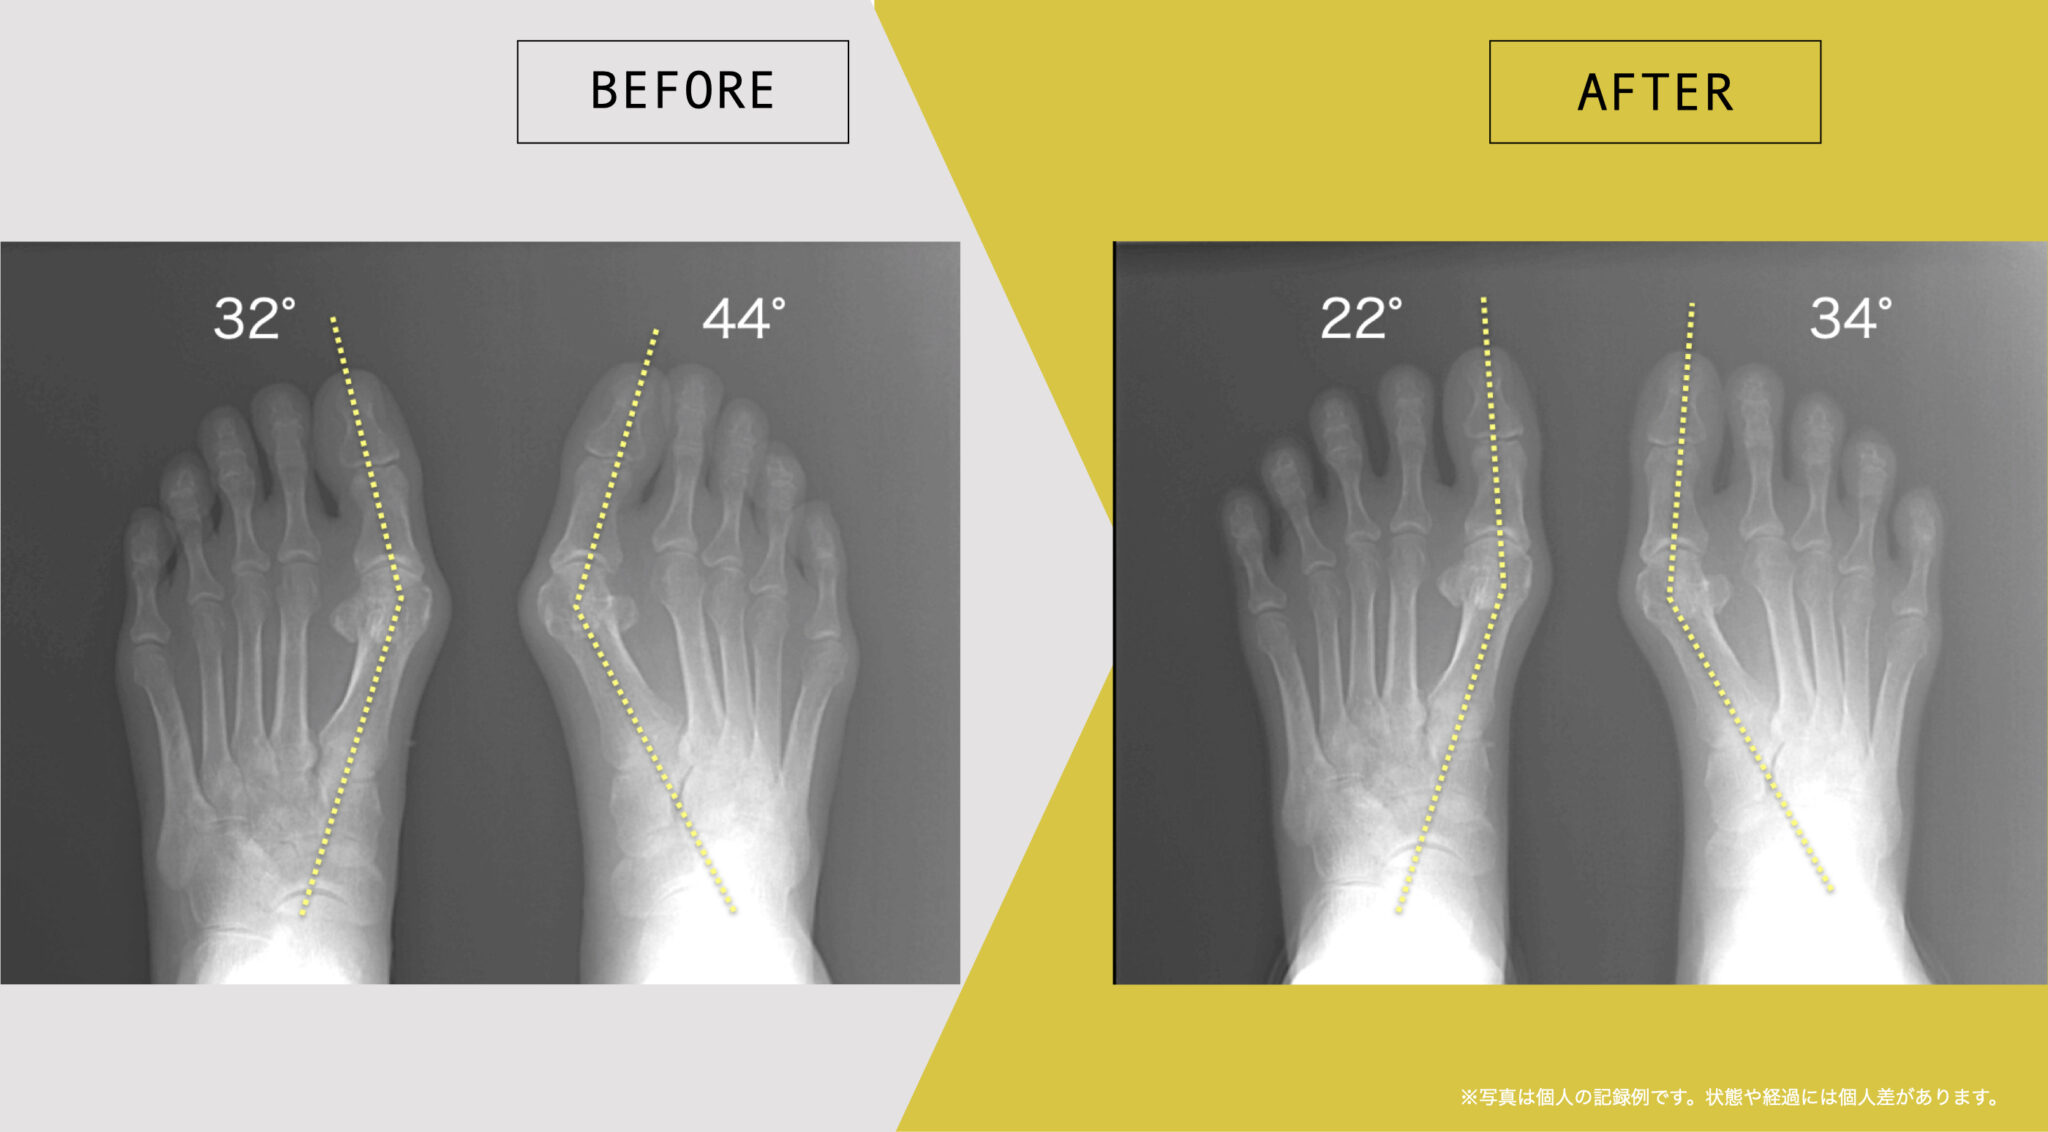

足指や姿勢の状態に関する記録例

ここでは、日常生活の中で足指のセルフケアを継続された方について、足指や姿勢の状態を記録した一例をご紹介します。

これらは、医療的な効果や症状の改善を示すものではなく、生活習慣の中での足指の状態を個別に記録した参考例です。同様の結果が得られることを示すものではなく、状態や経過には個人差があります。